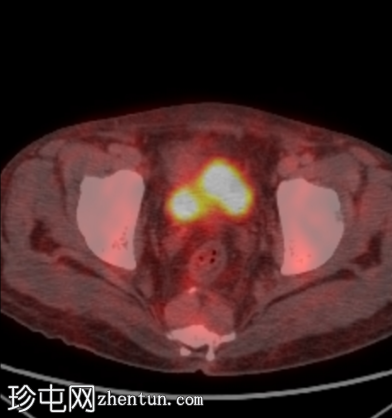

PET-CT

PET

轴位融合扫描

骨髓纤维化的经典三联征:

弥漫性骨硬化,FDG摄取轻度增高

脾肿大(23厘米),FDG摄取轻度增高(SUVmax 4)

椎旁(轴位和冠状位)、左侧主动脉旁和骶前区可见多个边界清晰的非FDG摄取肿块,内部可见脂肪衰减

双侧下叶肺实变,FDG摄取增高(SUVmax 7),可能为炎症性

心脏扩大和轻度双侧胸腔积液。

轻度肝肿大和胆结石

右侧肾上腺小结节无FDG摄取,直径10mm,平均衰减值为50 HU。